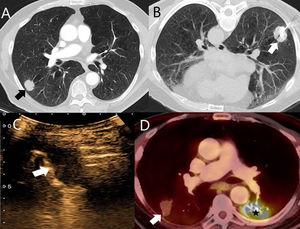

A) TC de tórax con contraste yodado intravenoso y ventana de pulmón. Se observa un nódulo subpleural sólido (flecha) en un paciente con enfermedad metastásica de un carcinoma escamoso cutáneo de células basales. Este nódulo se decidió tratar mediante ARF guiada por TC. B) Corte axial con el paciente en decúbito supino, durante la realización de la ARF guiada por TC. Se utilizó una aguja tipo «paraguas» (flecha). C) CEUS pulmonar de la misma lesión. No se observa captación de contraste durante todo el procedimiento, lo que indica una respuesta completa al tratamiento ablativo. D) PET-TC de tórax del mismo paciente un año después del tratamiento ablativo. Muestra disminución en el tamaño de la lesión tratada y ausencia de captación de FDG (flecha), concordante esto con una respuesta completa. Se observó un aumento patológico de la FDG en la lesión del lóbulo inferior izquierdo tratada con radioterapia (estrella).

El 30/01/2017 se realizó una ARF guiada por TC de los 2nódulos localizados en el lóbulo inferior derecho. Una lesión fue tratada con una aguja en forma de paraguas de 3 cm (fig. 1B), que presentó un neumotórax leve y un halo después del tratamiento, y la otra se trató con una aguja recta de 2 cm. En el control inmediato por TC se observó un neumotórax derecho que necesitó la colocación de un drenaje, dado que el paciente se encontraba disneico. Posteriormente el paciente presentó un derrame pleural derecho moderado, tratado mediante un drenaje pleural guiado por ecografía el 28/02/2017. Durante el procedimiento se llevó a cabo una CEUS pulmonar para valorar una potencial infección de la lesión tratada con ARF. La lesión no presentó captación de contraste ecográfico durante toda la exploración; este hallazgo fue sugestivo de corresponder a necrosis, lo que indicaba una respuesta completa al tratamiento con ARF (fig. 1C). Con los controles posteriores mediante TC y PET-TC se confirmó una respuesta completa hasta la fecha (10/01/2019) (fig. 1D).